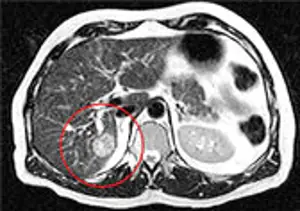

Лечение метастазов рака легкого в головном мозгу кибер-ножом

МРТ-изображение с двумя метастазами рака легкого в головной мозг

Оба метастаза были удалены за один сеанс, длительностью 1 час. На снимке результат контрольного обследования через 4 месяца после лечения. Обе опухоли были удалены, после лечения пациент в тот же день вернулся к работе